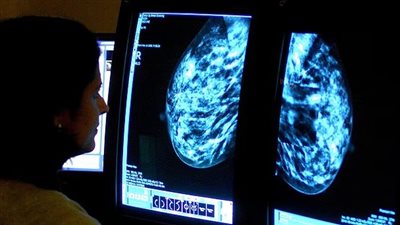

دراسة: الرمان يساعد في الوقاية من سرطان الثدي

وجدت الدراسة أن الرمان يحتوي على مواد قد تعيق تخليق هرمون الإستروجين، مما يحفز نمو الأورام الخبيثة. ويُعتبر ارتفاع هذا الهرمون سببًا لنمو الخلايا السرطانية في الغدد الثديية، بالإضافة إلى ذلك، يمكن أن ينتشر المرض في جميع أنحاء الجسم عبر الأوعية اللمفاوية وفي حال عدم اتخاذ إجراءات علاجية فعالة، ينتشر سرطان الثدي إلى العظام والكبد والرئتين والدماغ.